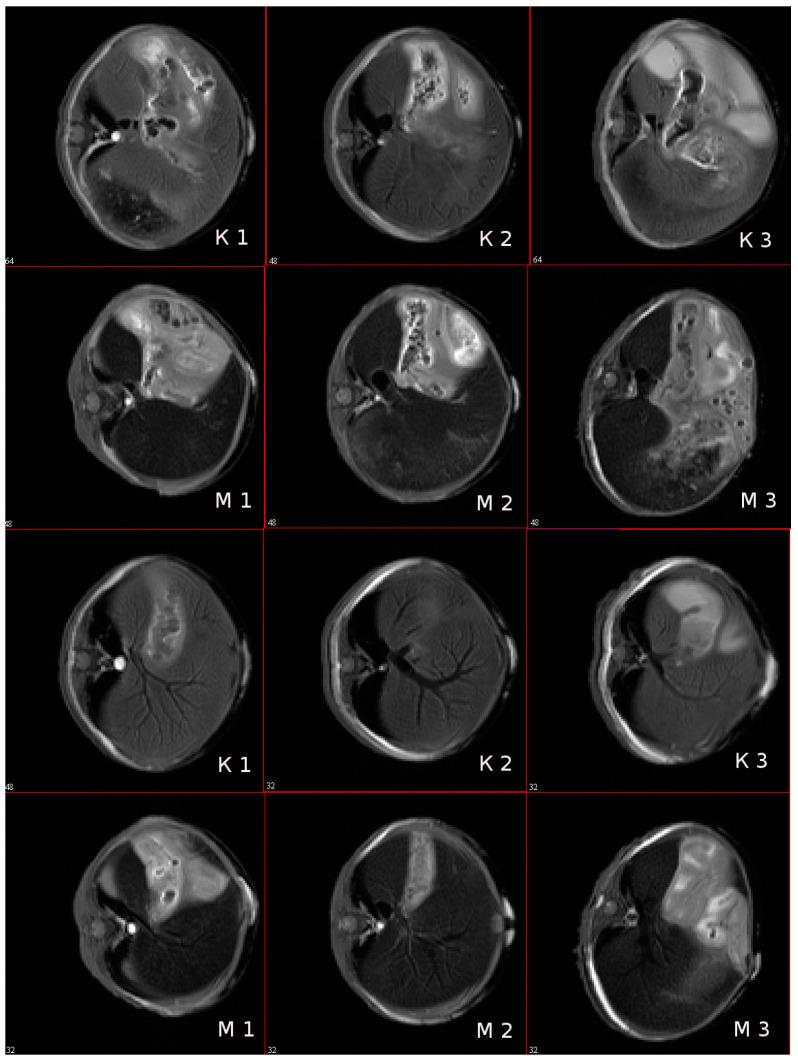

Type I interferons, particularly IFNα-2b, play essential roles in eliciting adaptive and innate immune responses, being implicated in the pathogenesis of various diseases, including cancer, and autoimmune and infectious diseases. Therefore, the development of a highly sensitive platform for analysis of either IFNα-2b or anti-IFNα-2b antibodies is of high importance to improve the diagnosis of various pathologies associated with the IFNα-2b disbalance. For evaluation of the anti-IFNα-2b antibody level, we have synthesized superparamagnetic iron oxide nanoparticles (SPIONs) coupled with the recombinant human IFNα-2b protein (SPIONs@IFNα-2b). Employing a magnetic relaxation switching assay (MRSw)-based nanosensor, we detected picomolar concentrations (0.36 pg/mL) of anti-INFα-2b antibodies. The high sensitivity of the real-time antibodies' detection was ensured by the specificity of immune responses and the maintenance of resonance conditions for water spins by choosing a high-frequency filling of short radio-frequency pulses of the generator. The formation of a complex of the SPIONs@IFNα-2b nanoparticles with the anti-INFα-2b antibodies led to a cascade process of the formation of nanoparticle clusters, which was further enhanced by exposure to a strong (7.1 T) homogenous magnetic field. Obtained magnetic conjugates exhibited high negative MR contrast-enhancing properties (as shown by NMR studies) that were also preserved when particles were administered in vivo. Thus, we observed a 1.2-fold decrease of the T2 relaxation time in the liver following administration of magnetic conjugates as compared to the control. In conclusion, the developed MRSw assay based on SPIONs@IFNα-2b nanoparticles represents an alternative immunological probe for the estimation of anti-IFNα-2b antibodies that could be further employed in clinical studies.

I 型干扰素,特别是 IFNα-2b,在引发适应性和先天免疫反应方面发挥着重要作用,与包括癌症、自身免疫和传染病在内的各种疾病的发病机制有关。因此,开发一种高度敏感的分析平台,用于分析 IFNα-2b 或抗 IFNα-2b 抗体,对于改善与 IFNα-2b 失衡相关的各种病理的诊断具有重要意义。为了评估抗 IFNα-2b 抗体水平,我们合成了超顺磁性氧化铁纳米粒子(SPIONs)与重组人 IFNα-2b 蛋白(SPIONs@IFNα-2b)偶联。我们采用基于磁共振弛豫切换检测(MRSw)的纳米传感器,检测出皮摩尔浓度(0.36 pg/mL)的抗-INFα-2b 抗体。通过选择高频填充短射频脉冲发生器,保证了免疫反应的特异性和水自旋的共振条件,实现了实时抗体检测的高灵敏度。SPIONs@IFNα-2b 纳米粒子与抗-INFα-2b 抗体形成复合物,导致纳米粒子簇的级联形成,进一步通过暴露于强(7.1 T)均匀磁场得到增强。所获得的磁性结合物表现出高的负磁共振对比增强特性(如 NMR 研究所示),当颗粒在体内给药时也得到保留。因此,与对照组相比,在给予磁性结合物后,我们观察到肝脏的 T2 弛豫时间降低了 1.2 倍。总之,基于 SPIONs@IFNα-2b 纳米粒子的开发的 MRSw 检测方法代表了一种替代免疫探针,用于估计抗 IFNα-2b 抗体,可进一步用于临床研究。